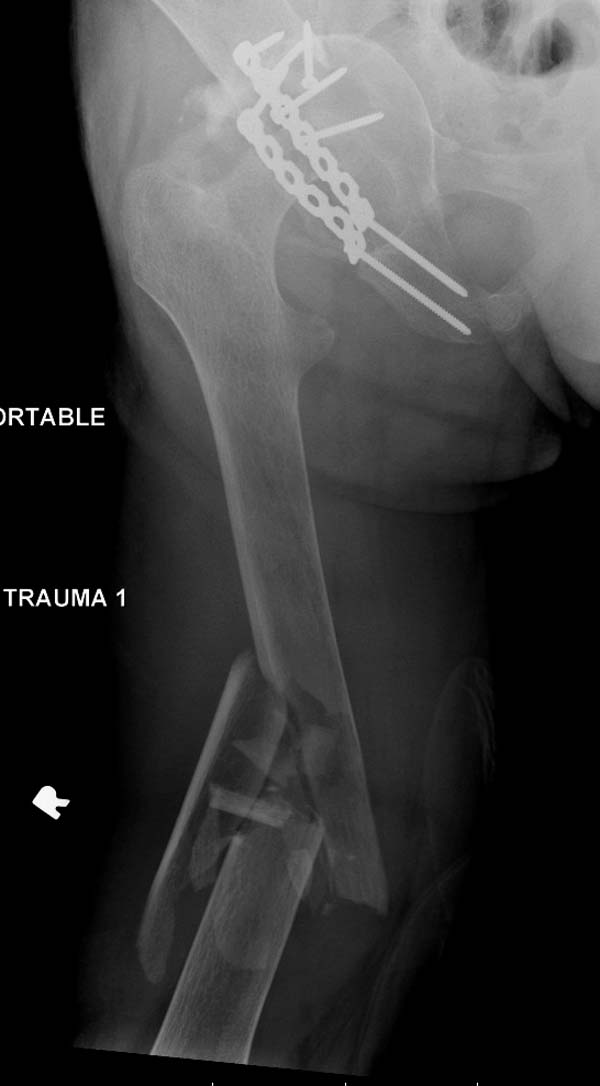

Больному 25 лет, транспортная травма. С детства хроническая почечная

недостаточность, постоянный гемодиализ, находится в листе ожидания на

пересадку почки. Около 4 года назад автоавария с двухсторенним переломом

ацетабулум, которая слева закончилось тотальным протезированием.

Диагноз: переломы бедренных костей, перелом дистального плеча слева,

также неосложненный перелом на уровне грудных позвонков.

Рентген снимки. Хотели услышать примерный алгоритм лечения, c чего

начать и как?

Имя     : 3 Periprosthetic IM nail Lt femur 2.jpg